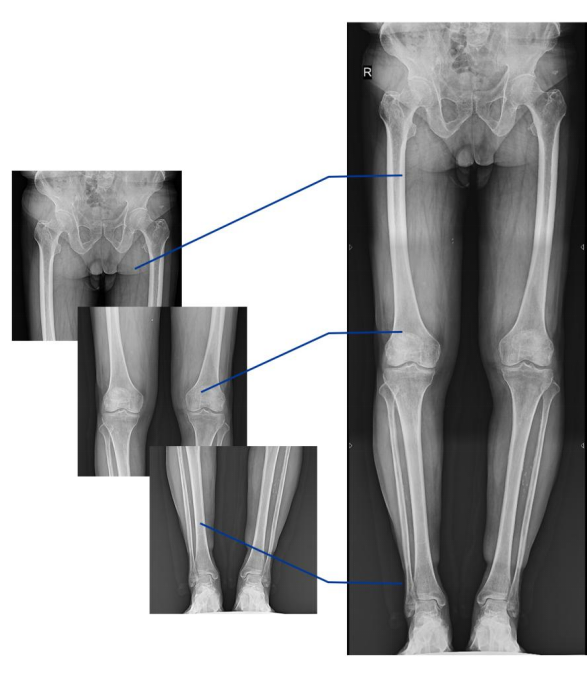

不同于常規(guī)靜態(tài)DR只能進行平片攝影檢查,動態(tài)DR可以滿足多種臨床檢查需求,包括靜態(tài)檢查、透視檢查、造影檢查、脊柱及下肢全長拼接檢查,相較于靜態(tài)DR具有豐富的臨床應(yīng)用,且動態(tài)DR檢查更精準(zhǔn)、直觀,擺位攝片效率極大地提升,大大節(jié)省拍片時間。

動態(tài)DR影像采集幅面大,17×17英寸超大視野,可覆蓋成年人的全胸全腹,并且能在連續(xù)動態(tài)中實時高清點片,還可以進行視頻保存,在會診過程中可以回放影像檢查視頻,從而達到精準(zhǔn)診斷的目的。同時動態(tài)DR還具有全身拼接功能,尤其適用于全脊柱和全下肢攝影,輔助脊柱畸形矯形治療、康復(fù)檢查,為臨床提供高精度圖像。